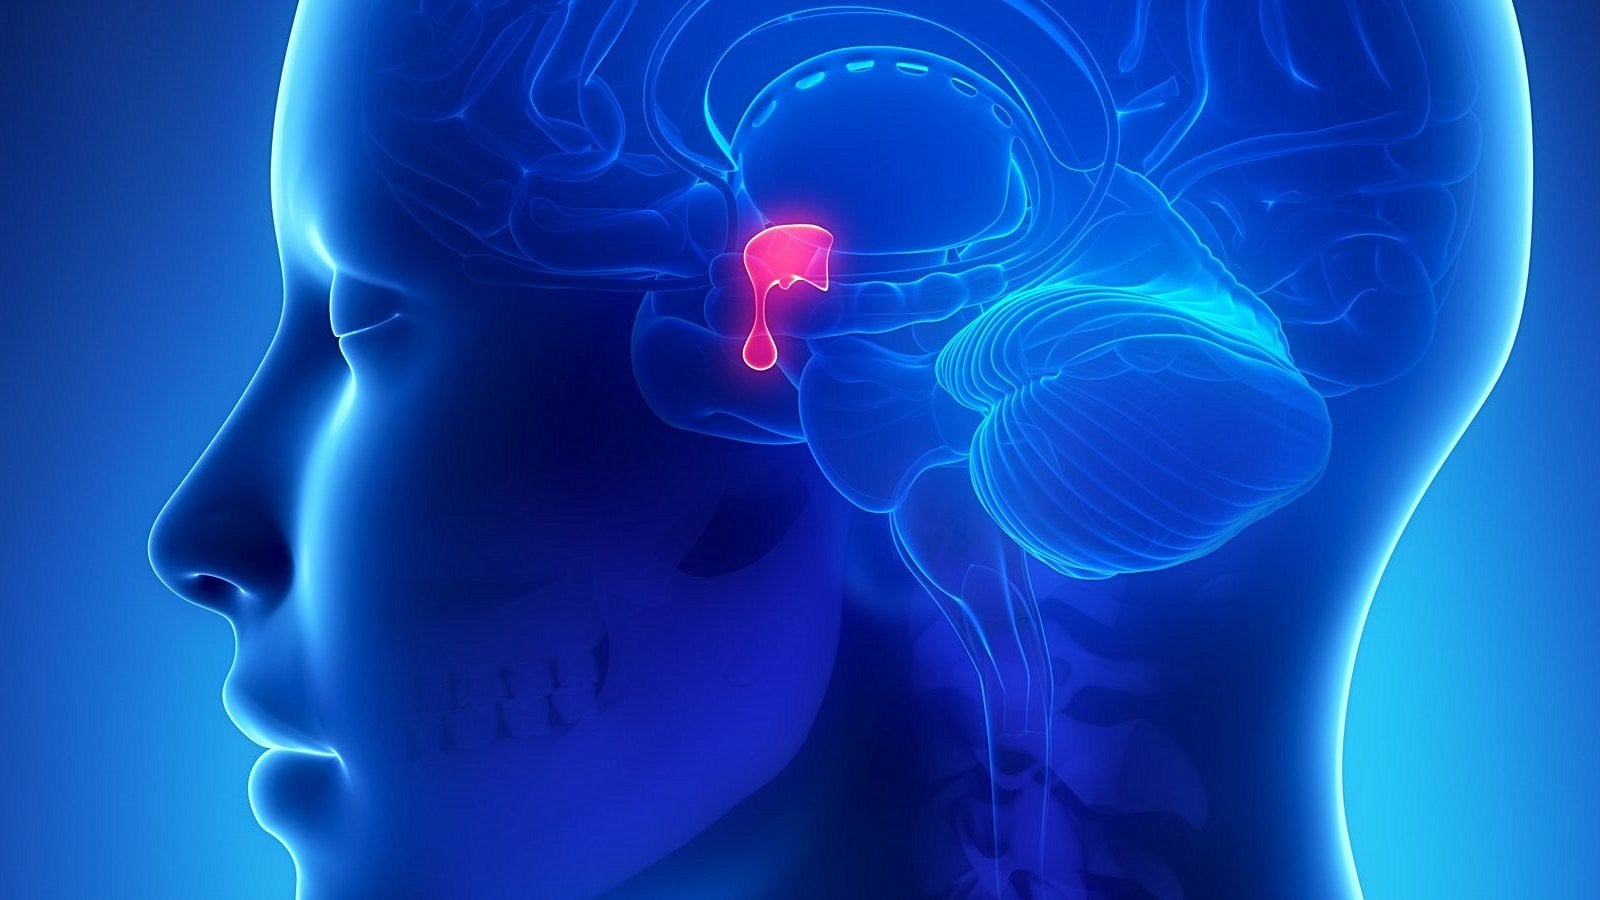

Hipofiz; bezelye büyüklüğünde, yaklaşık 0,5 gram ağırlığında, hipotalamusun altında ve sella turcica'ya yerleşmiş vaziyette bir endokrin bezdir. Salgıladığı hormonlarla vücudumuzdaki çeşitli fizyolojik süreçlerin düzenlenmesinde kritik rol alır. Hamilelik sırasında değişen biyolojik koşullar ve hormonal gereksinimler hipofiz bezinde bir dönüşüm meydana getirir.

Hipofiz bezi gebelik süresince, gebelik öncesi boyutuna göre ciddi oranda büyür. Kesit alanı ve ağırlığı yaklaşık olarak %33 artar.[1] Bu artış daha çok prolaktin hormonu üreten laktotrop hücreler tarafından gerçekleşir. Hipofiz bezi gebelik süresince bu kadar hızlı büyümesine rağmen kanlanması aynı oranda artmaz ve iskemiye (kan akımının azalması veya tamamen kesilmesi sonucu hayati moleküllere erişimin engellenmesi durumu) duyarlı hale gelir.